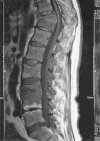

Musculoskeletal tuberculosis (TB) accounts for approximately 10% of all extrapulmonary TB cases in the United States and is the third most common site of extrapulmonary TB after pleural and lymphatic disease. Vertebral involvement (tuberculous spondylitis, or Pott's disease) is the most common type of skeletal TB, accounting for about half of all cases of musculoskeletal TB. The presentation of musculoskeletal TB may be insidious over a long period and the diagnosis may be elusive and delayed, as TB may not be the initial consideration in the differential diagnosis. Concomitant pulmonary involvement may not be present, thus confusing the diagnosis even further. Early diagnosis of bone and joint disease is important to minimize the risk of deformity and enhance outcome. The introduction of newer imaging modalities, including MRI (imaging procedure of choice) and CT, has enhanced the diagnostic evaluation of patients with musculoskeletal TB and for directed biopsies of affected areas of the musculoskeletal system. Obtaining appropriate specimens for culture and other diagnostic tests is essential to establish a definitive diagnosis and recover M. tuberculosis for susceptibility testing. A total of 6 to 9 months of a rifampin-based regimen, like treatment of pulmonary TB, is recommended for the treatment of drug susceptible musculoskeletal disease. Randomized trials of tuberculous spondylitis have demonstrated that such regimens are efficacious. These data and those from the treatment of pulmonary TB have been extrapolated to form the basis of treatment regimen recommendations for other forms of musculoskeletal TB.